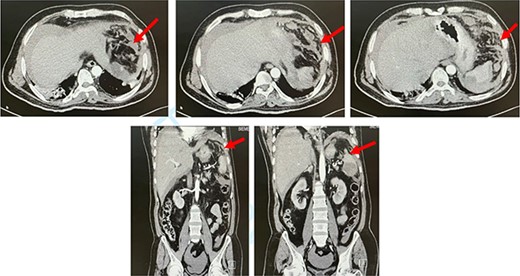

CT abdomen. Axial and coronal views showing splenic rupture and hemoperitoneum (red arrow).

The next day, the patient deteriorated clinically and became hemodynamically unstable. His abdomen was distended with generalized guarding and tenderness. His labs showed leukocytosis and hemoglobin drop from 12 g/dl to 9 g/dl. After resuscitation, CT of the abdomen was performed and showed a large splenic infarct with perisplenic hematoma, contrast extravasation and hemoperitoneum (Fig. 1). The patient deteriorated after CT and became vitally unstable, with low GCS 6, with further drop in hemoglobin to 6 g/dl. The patient was intubated and shifted to ICU for circulatory and respiratory support. He was taken to the operating room and underwent exploratory laparotomy. Upon exploration, 2 L of fresh blood was found in the abdomen, with multiple areas of splenic laceration and rupture. Packing was performed for bleeding control and was followed by splenectomy. Microscopic examination showed areas of extensive necrosis and areas of hemorrhage with blood clots.